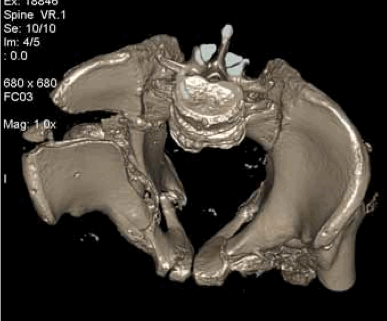

- фиксация ламинектомированного фрагмента по линии остеотомии сетчатой пластиной (Фиг. 2 - представлена обзорная рентгенограмма таза (а) и КТ сканы в сагиттальной (б) и горизонтальной (в) плоскости после операции. После операции пациентка активизирована на третьи сутки, рана заживлена первичным натяжением, швы сняты не 12 сутки. Проводилась медикаментозная и электоронейростимуляция. Выписана из стационара на 17 сутки после операции.

На контрольном осмотре через 1 месяц после операции пациентка жалоб не предъявляла. Достигнуты: полный регресс неврологической симптоматики, консолидация переломов костей таза. Получен хороший функциональный результат.